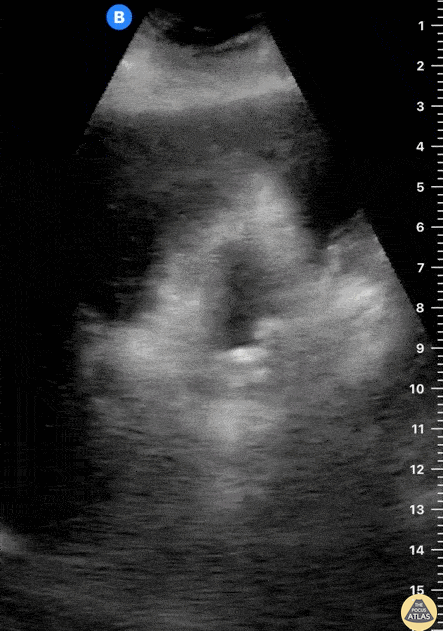

Biliary - Cholelithiasis - Multiple Stones

The gallbladder is studied in both planes, revealing multiple small stones generating acoustic shadowing. Dr. Felipe Urriola P